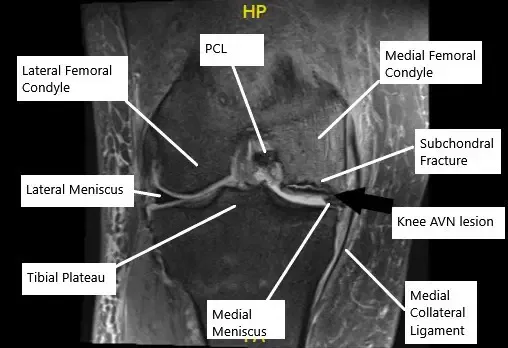

MRI of the knee in the coronal section showing AVN lesion along with subchondral fracture in the medial femoral condyle.

- MRI: MRI is the most sensitive tool for diagnosing AVN, revealing changes in bone structure, subchondral fractures, and early signs of bone death.